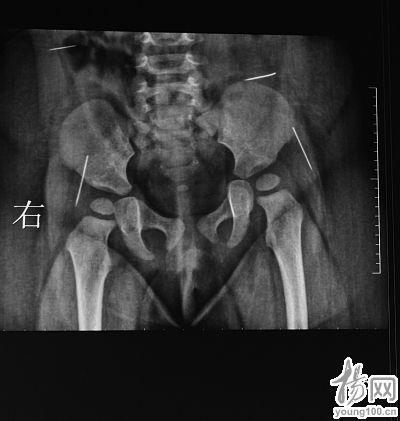

X片显示,萌萌体内有四根针状金属物

陈医生告诉记者,看着襁褓里哭闹不已的女婴,他首先对女婴进行初步检查,发现她的臀部有一明显的针眼,而且有点感染,后经女婴父母介绍他才得知,7月22日,由于萌萌一直哭闹,家人在她的臀部发现一根没有针鼻的缝衣针,于是送到淮安市第一人民医院将这根冒出体外的缝衣针给拔掉了,该院也为女婴拍了一次X片,X片显示女婴体内还有四根针状金属物,医院建议到妇幼保健院做手术。

“有一点是肯定的,这四根缝衣针都是通过外力作用被戳进萌萌体内的”,陈卫兵告诉记者,从取出的缝衣针所附的体液颜色以及缝衣针所处体内位置的感染程度来看,这四根缝衣针在萌萌体内至少一个多月了。在萌萌手术前所拍的CT片上,清晰可见四个白亮亮长短不一的缝衣针,所处的位置分别在腰部和臀部两侧。陈卫兵告诉记者,臀部的两根缝衣针非常危险,已经移动到髋关节之间,有可能触及萌萌的坐骨神经,处于腰部的那根更危险,因为眼看着就要移动到肝脏位置。

在放射科,记者看到了萌萌手术前所拍的CT片,放射科主任鸥继华指着一张能看出缝衣针在萌萌体内一运动轨迹的片子告诉记者,这根缝衣针现在所处的位置已在接近臀部的髋关节,从运动轨迹来看,不排除是人为地从上往下戳进去的,而且取出的四根都没有针鼻,如果真的是人为的,那戳针的人还很有心计,因为如果不把针鼻去掉,那么整根缝衣针戳进皮肤后,由于针鼻有个小孔会造成缝衣针在进入萌萌体内时造成一定的阻力,缝衣针也就不会很快进入体内。四根缝衣针入体运动轨迹周围的软组织都已受感染。鸥主任告诉记者,他从事这么多年的放射工作,在一个人的体内,尤其是11个月大女婴的体内发现四根缝衣针还是头一次。